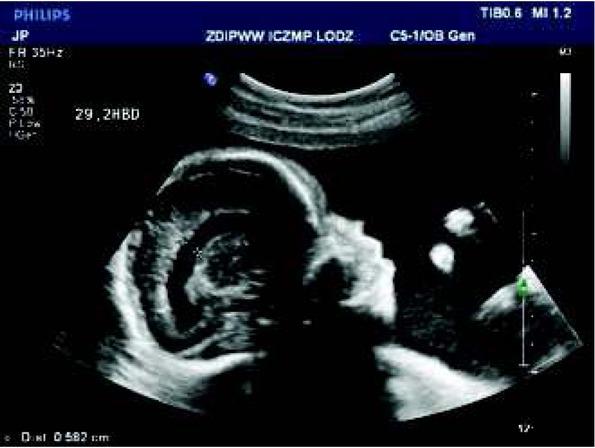

Fig. 4

Abnormal view of the fetal heart at 29th week of gestation with pericardial effusion of 5 mm – one of the signs of congestive heart failure and fibroelastosis of enlarged left ventricle.Ryc. 4. W 29 tyg. nieprawidłowy obraz serca płodu z cechami niewydolności krążenia – wysięk w osierdziu 5 mm oraz fibroelastoza powiększonej lewej komory serca.